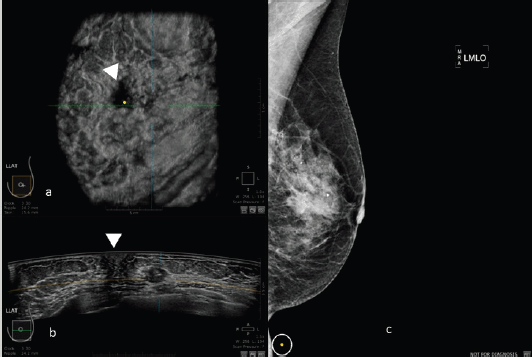

Images of comparison between ABUS, HHUS and mammography are shown in Figures 2 and 3.

Figure 3. 50-year-old patient with biopsy proven left breast carcinoma. a: 3D ultrasound (ABUS) image at the dedicated workstation. Reconstructed coronal plane: the lesion is marked as a reference point. The nipple is marked with the arrowhead. b: 3D ultrasound (ABUS) image at the dedicated workstation. Reconstructed axial plane: the lesion is marked as a reference point. The nipple is marked with the arrowhead. c: Full field digital mammography of the left breast in which the lesion is fairly visible.